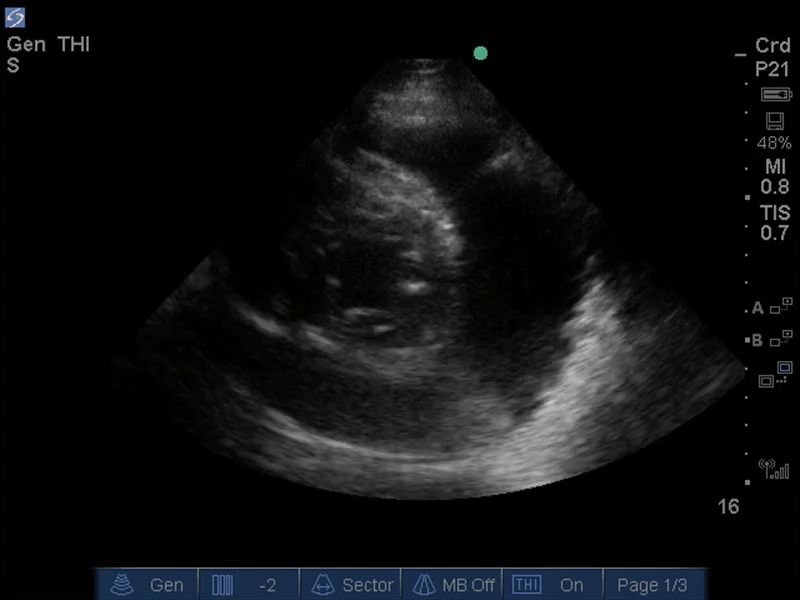

TEE 心包图像